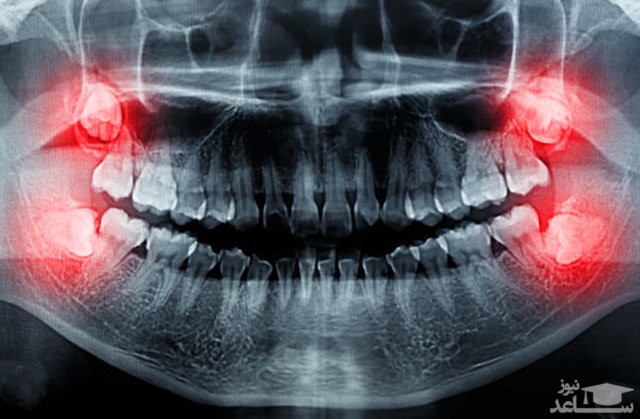

کشیدن دندان عقل نهفته، یک عمل جراحی است و مراقبت های بعد از کشیدن دندان عقل بسیار مهم است. در صورتی که توصیه های دندانپزشک به درستی رعایت شود، درد و مشکلات و ورم صورت بعد از کشیدن دندان به حداقل می رسد.